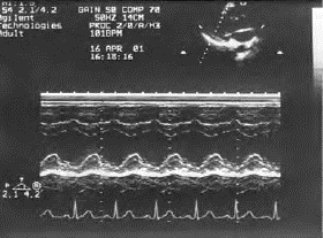

2.室壁收缩运动延迟 局部室壁收缩时相较正常室壁延迟,常以M型检测,并与心电图对比。心肌缺血部位局部收缩时相较正常心肌延缓。M型心动图可显示收缩时相落后于正常心肌室壁运动幅度可能减弱,也可能不减弱(图19-8)。

图19-8 室壁运动延迟M型运动曲线

显示左室下壁幅度降低,与心电图及室间隔运动曲线比较,收缩延迟